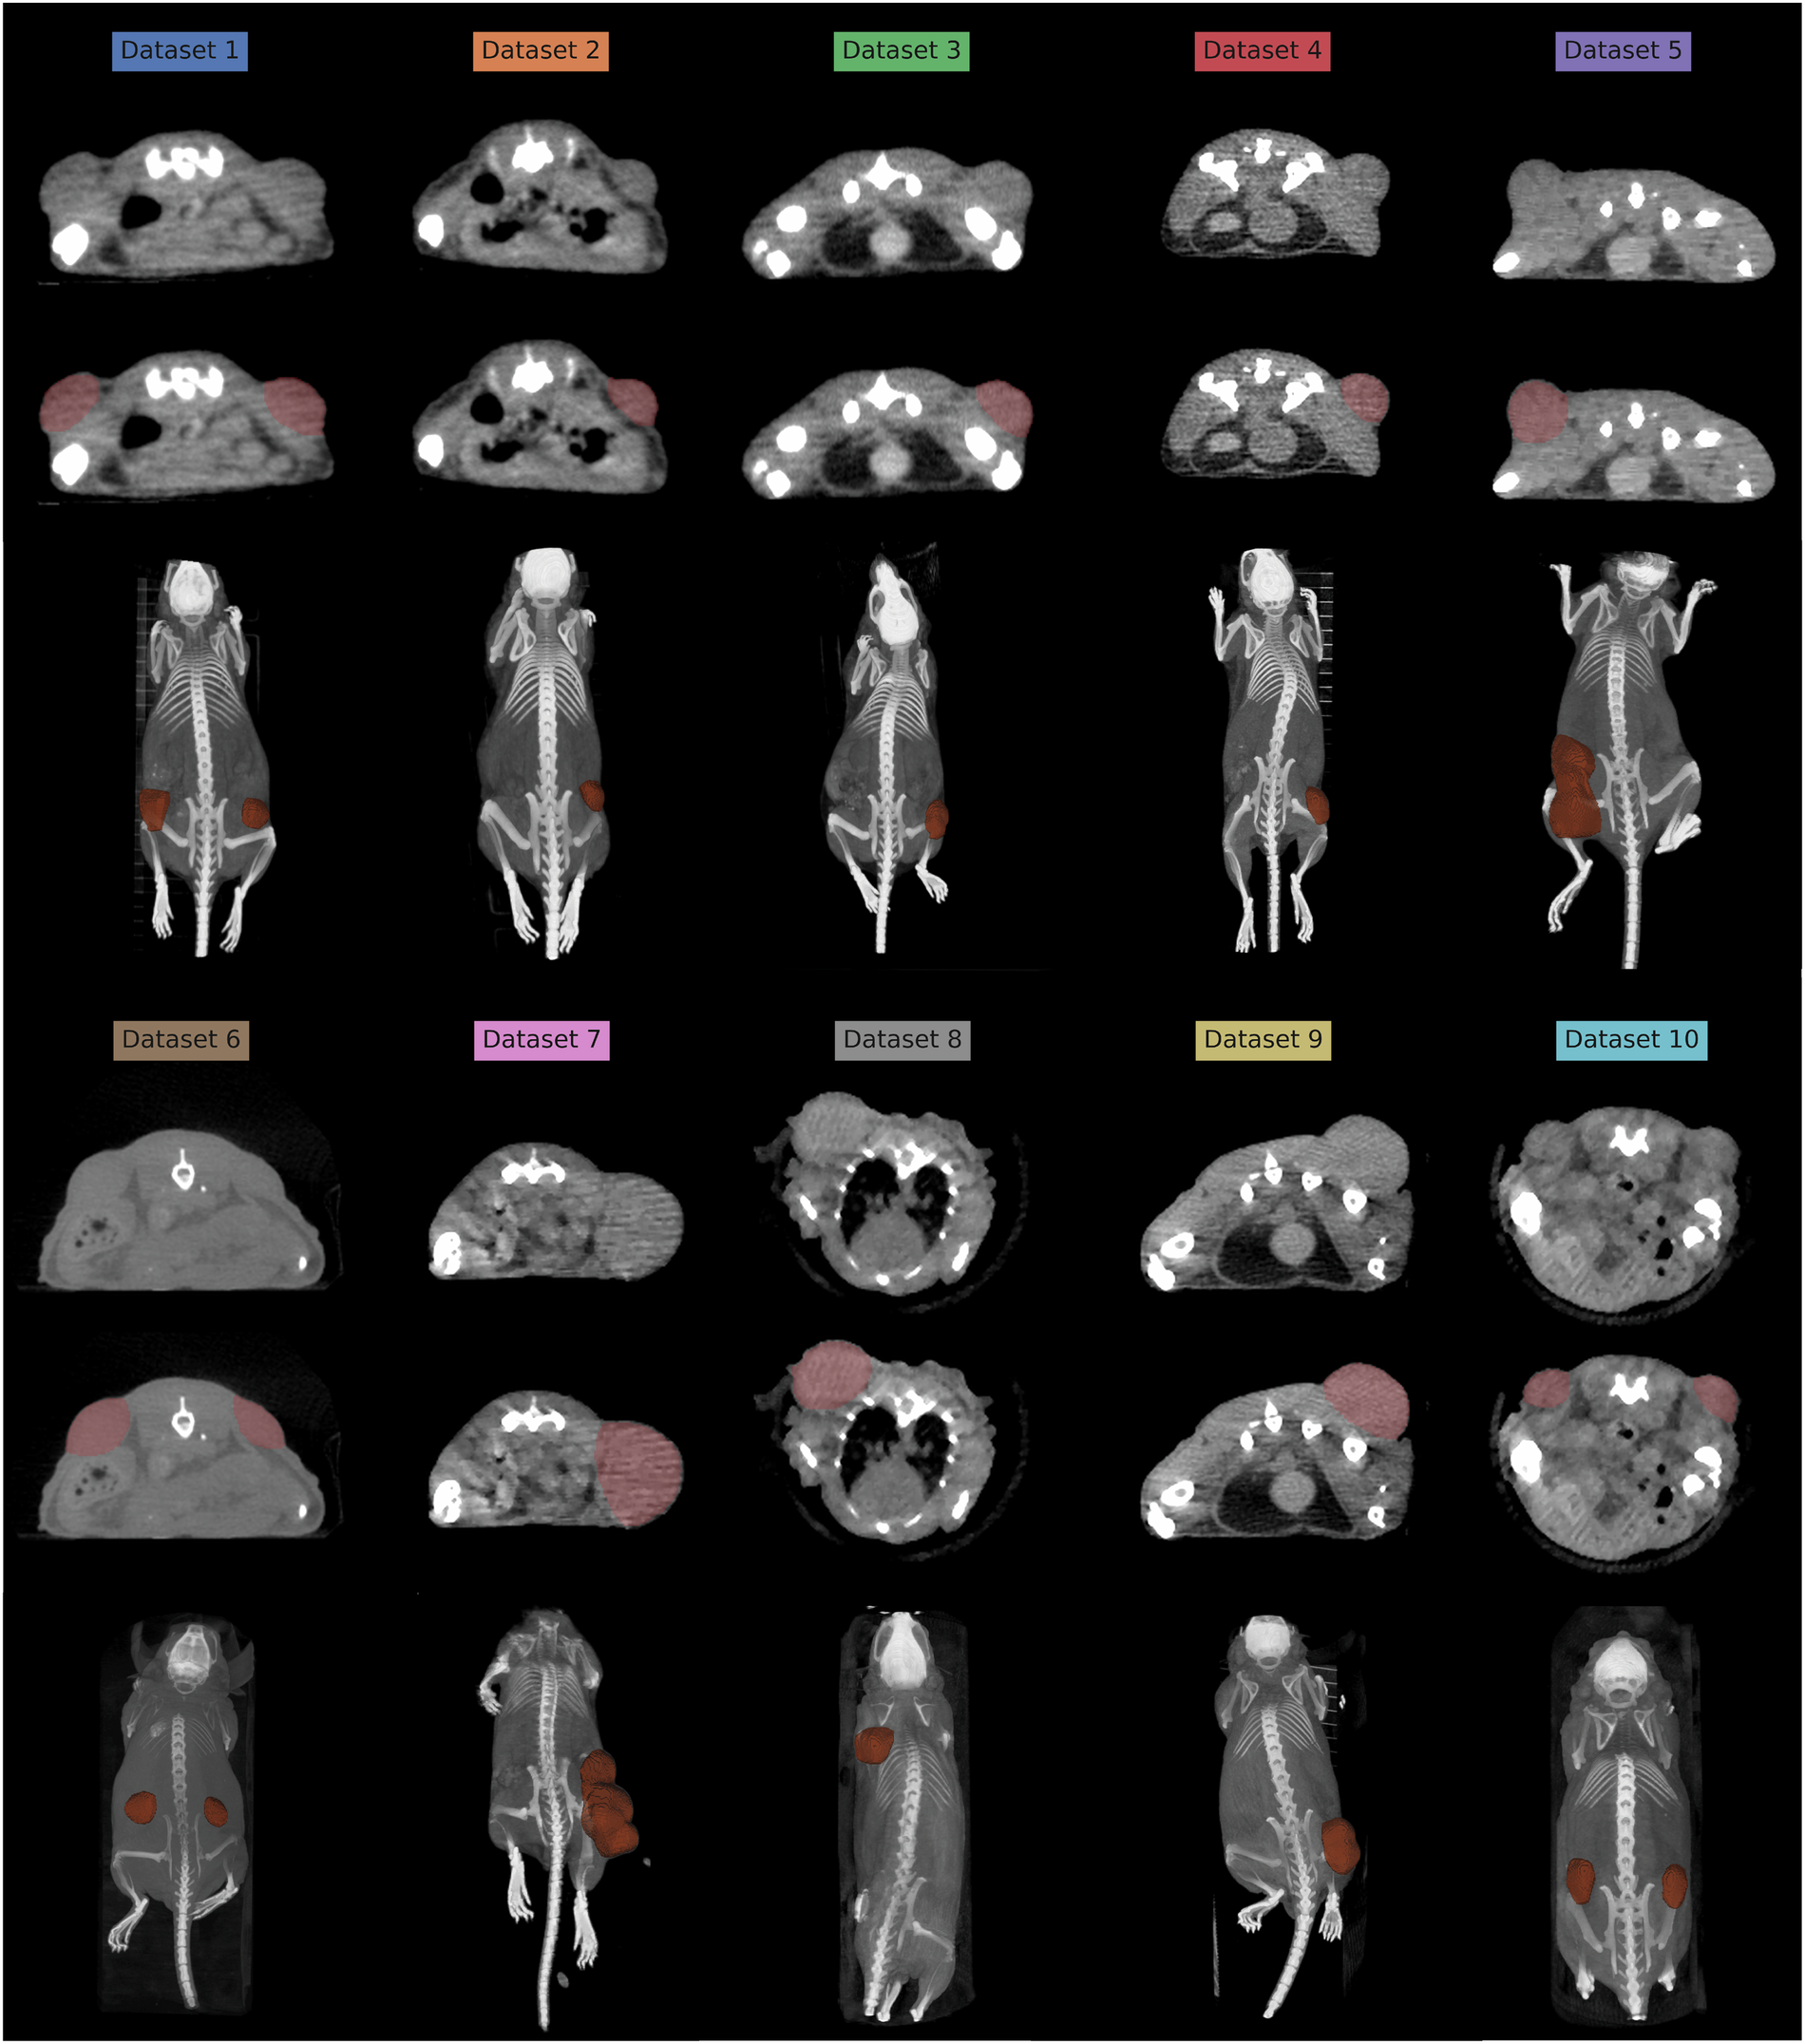

Example of a µCT scan for each of the 10 datasets, with an axial slice containing the tumor with and without the tumor mask overlayed in red, and a 3D Maximum Intensity Projection of the entire scan shown below the axial slices.